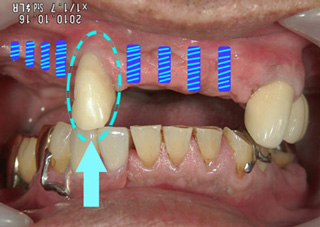

インプラントのために抜歯する? この1本を抜歯するか?それとも保存するか? 当コラムでは初登場の、インプラントのケースです。 11月早々に、インプラントの手術をおこなう患者さまのお口です。

濃いブルーのラインが、インプラントの予定位置です。

矢印で示すように、健康な前歯が真ん中に1本残っています。

インプラント治療の手術を行う場合、この残った歯は

型取りが、困難・複雑になる

この歯が歯周病になった場合、それが周りのインプラントに感染する

など、管理の難しい存在となります。